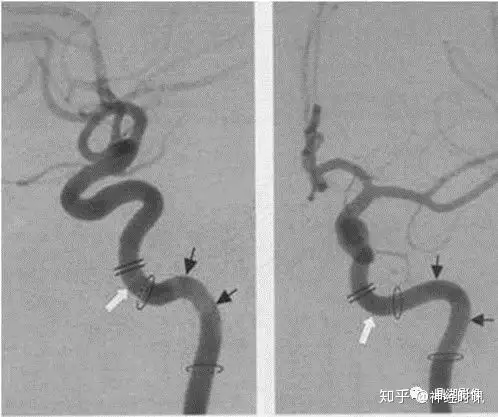

各种颅内出血

几种类型脑出血的CT表现